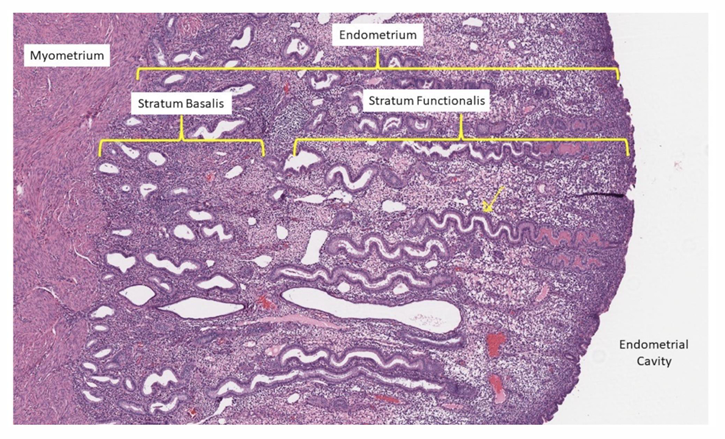

uterine anatomy